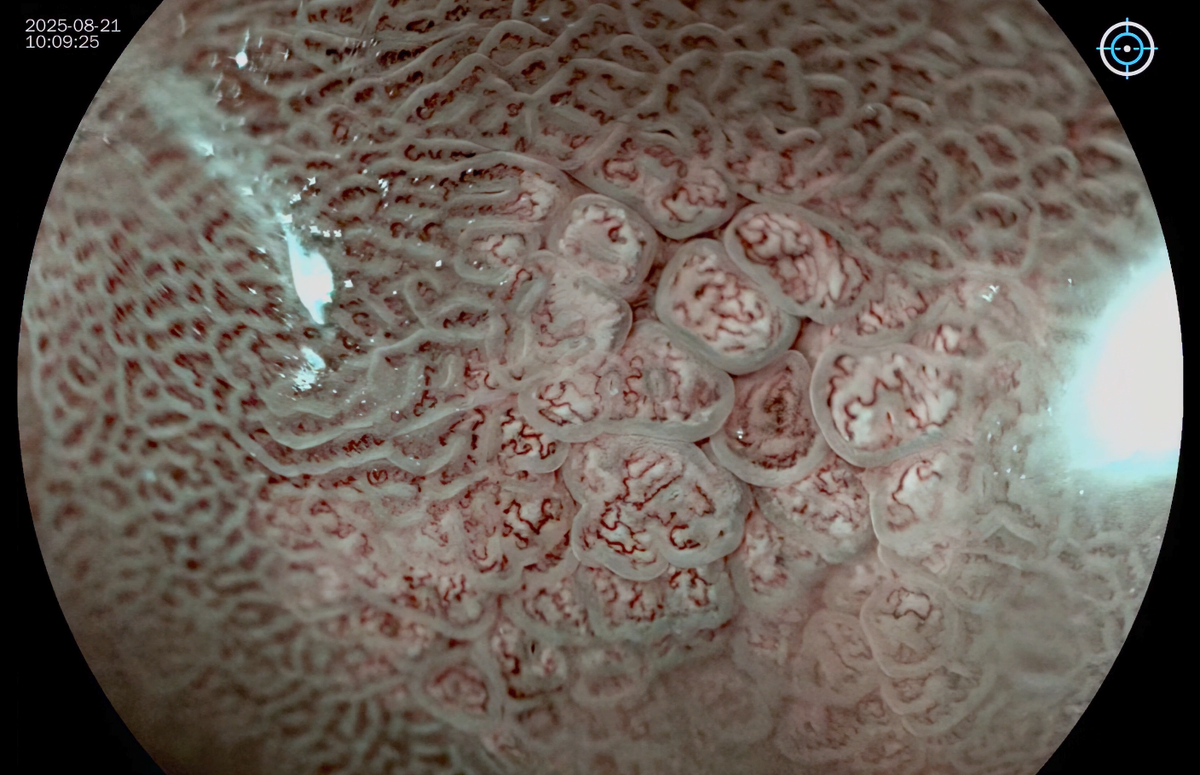

ЭндоскопичСская ΠΊΠ°Ρ€Ρ‚ΠΈΠ½Π°

βœ”οΈ Π€ΠΎΡ€ΠΌΠ°: плоская Π»ΠΈΠ±ΠΎ слСгкая Π²ΠΎΠ·Π²Ρ‹ΡˆΠ°ΡŽΡ‰Π°Ρ, ΠΌΠΎΠΆΠ΅Ρ‚ Π±Ρ‹Ρ‚ΡŒ чСчСвицСобразная Π»ΠΈΠ±ΠΎ полиповидная

βœ”οΈ Π“Ρ€Π°Π½ΠΈΡ†Ρ‹: Ρ‡Π΅Ρ‚ΠΊΠΈΠ΅

βœ”οΈ Π Π°Π·ΠΌΠ΅Ρ€: ΠΎΡ‚ 0,1 Π΄ΠΎ 1,5 см.

βœ”οΈ Π¦Π²Π΅Ρ‚: ΠΎΡ‚ Π±Π΅Π»ΠΎΠ³ΠΎ Π΄ΠΎ Π±Π»Π΅Π΄Π½ΠΎ-ΠΆΠ΅Π»Ρ‚ΠΎΠ³ΠΎ ΠΈ ΠΎΡ€Π°Π½ΠΆΠ΅Π²ΠΎΠ³ΠΎ.

βœ”οΈ ΠšΠΎΠ»ΠΈΡ‡Π΅ΡΡ‚Π²ΠΎ: ΠΌΠΎΠ³ΡƒΡ‚ Π±Ρ‹Ρ‚ΡŒ ΠΌΠ΅Π»ΠΊΠΈΠΌΠΈ ΠΎΠ΄ΠΈΠ½ΠΎΡ‡Π½Ρ‹ΠΌΠΈ, мноТСствСнными ΠΈ ΠΌΠΎΠ³ΡƒΡ‚ ΠΏΡ€Π΅Π΄ΡΡ‚Π°Π²Π»ΡΡ‚ΡŒ Π³Ρ€ΡƒΠΏΠΏΡ‹ ΠΈΠ· Π½Π΅ΡΠΊΠΎΠ»ΡŒΠΊΠΈΡ… ΠΌΠ΅Π»ΠΊΠΈΡ… ΠΈΠ»ΠΈ Ρ€Π°Π·Π½ΠΎΠ³ΠΎ Ρ€Π°Π·ΠΌΠ΅Ρ€Π° бляшСк

Π’ΠΈΠ΄Π΅ΠΎ снято с использованиСм гастроскопа VG-H1000Z Concemed с оптичСским ZOOM.